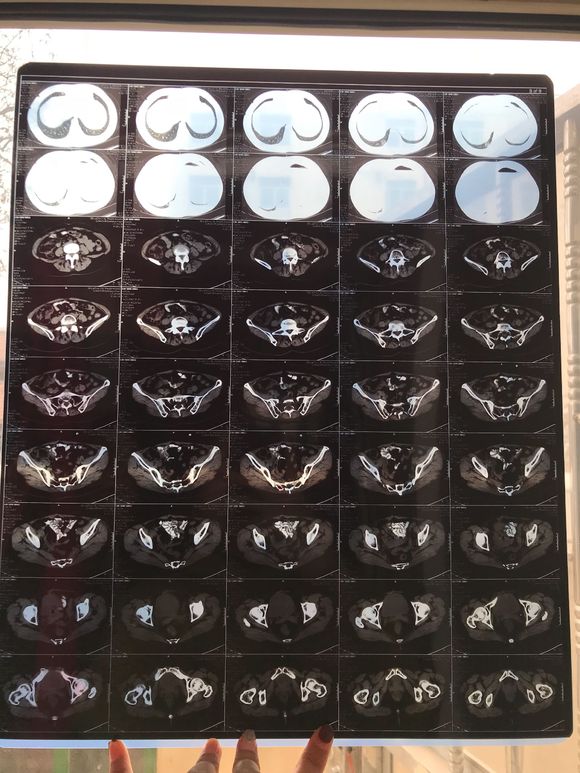

和你的故事 02019-04-09 患者家属我妈妈的病理结果报告,3期c1,大家可以帮忙看看吗,跪求了!我很急,谢谢!想知道是否严重,目前等术后出院后去肿瘤医院...

0人关注 4个回复 3515次浏览 -